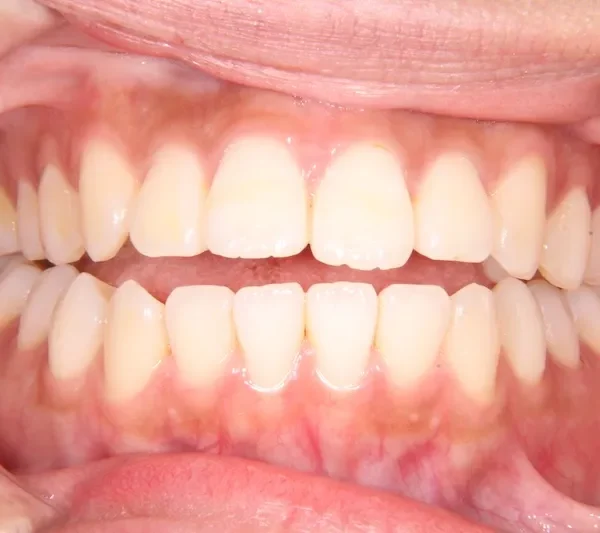

初診時

初診時年齢 19~29歳 (女性) 主訴 前歯で物が噛みちぎれない

診断名 開咬・上顎前突 装置名

前歯で物が噛みちぎれないを主訴に来院された患者様です。

非抜歯で、オリジナルリンガルアーチと歯科矯正用アンカースクリューを用いて治療しました。

治療回数15回、1年の治療期間で矯正治療を終了しました。

主訴が改善され、ご満足頂きました。